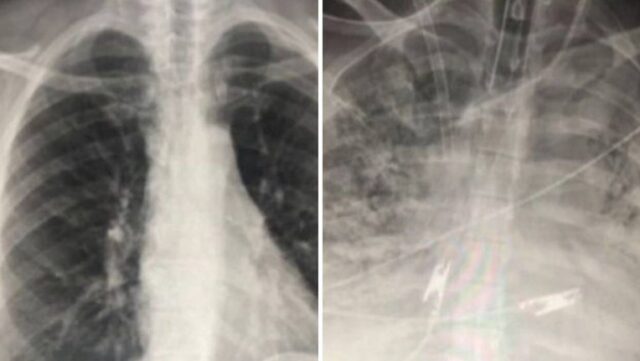

Ove rendgenske snimke prikazuju pluća dva pacijenta – oba su zaražena koronavirusom. Jedan je cijepljen, a drugi nije.

“Ozbiljno obolijevaju jedino necijepljeni. Njima često trebaju kisik ili moraju na respirator. Cijepljeni pacijenti zaraženi koronom imaju bolji protok zraka u plućima i veći dio pluća obojen im je u crno na ovim snimkama, što znači da je šteta na plućima mala ili nikakva”, rekao je liječnik Sam Durrani za Mirror, a oni su slike i objavili.

Kod necijepljenog pojedinca se vidi kako su pluća prilično oštećena te da je protok zraka ograničen.